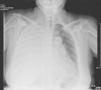

We present the case of a 59-year-old woman with a history of normal-pressure hydrocephalus requiring treatment with VP shunting. Eight years later, the patient underwent abdominal surgery due to acute perforated diverticulitis. The post-surgery evolution was torpid, with episodes of repetitive meningitis and a nasal CSF fistula. Given the said complications and the previous abdominal surgery, a decision is made to place a programmable VPL shunt. After a few months, the patient was admitted to the ICU due to progressive respiratory failure, even at rest, with criteria for severity. Upon auscultation, the patient presented diminished vesicular murmur in the right hemithorax, and chest radiography revealed a massive right pleural effusion (Fig. 1). Thoracocentesis was performed and an intrathoracic drain tube was inserted. The liquid presented biochemical characteristics compatible with hydrothorax. After increasing the pressure of the valve aperture and the evacuation of the effusion, the later evolution was satisfactory.